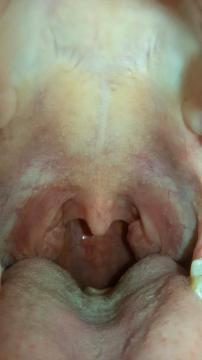

Dobrý den, prosím pomozte mi co to mám, jestli je to normální nebo ne:-( nemám je mi dobře, jen mě občas bolí hlava a polykání

Vaše mandle vypadají být v pořádku.